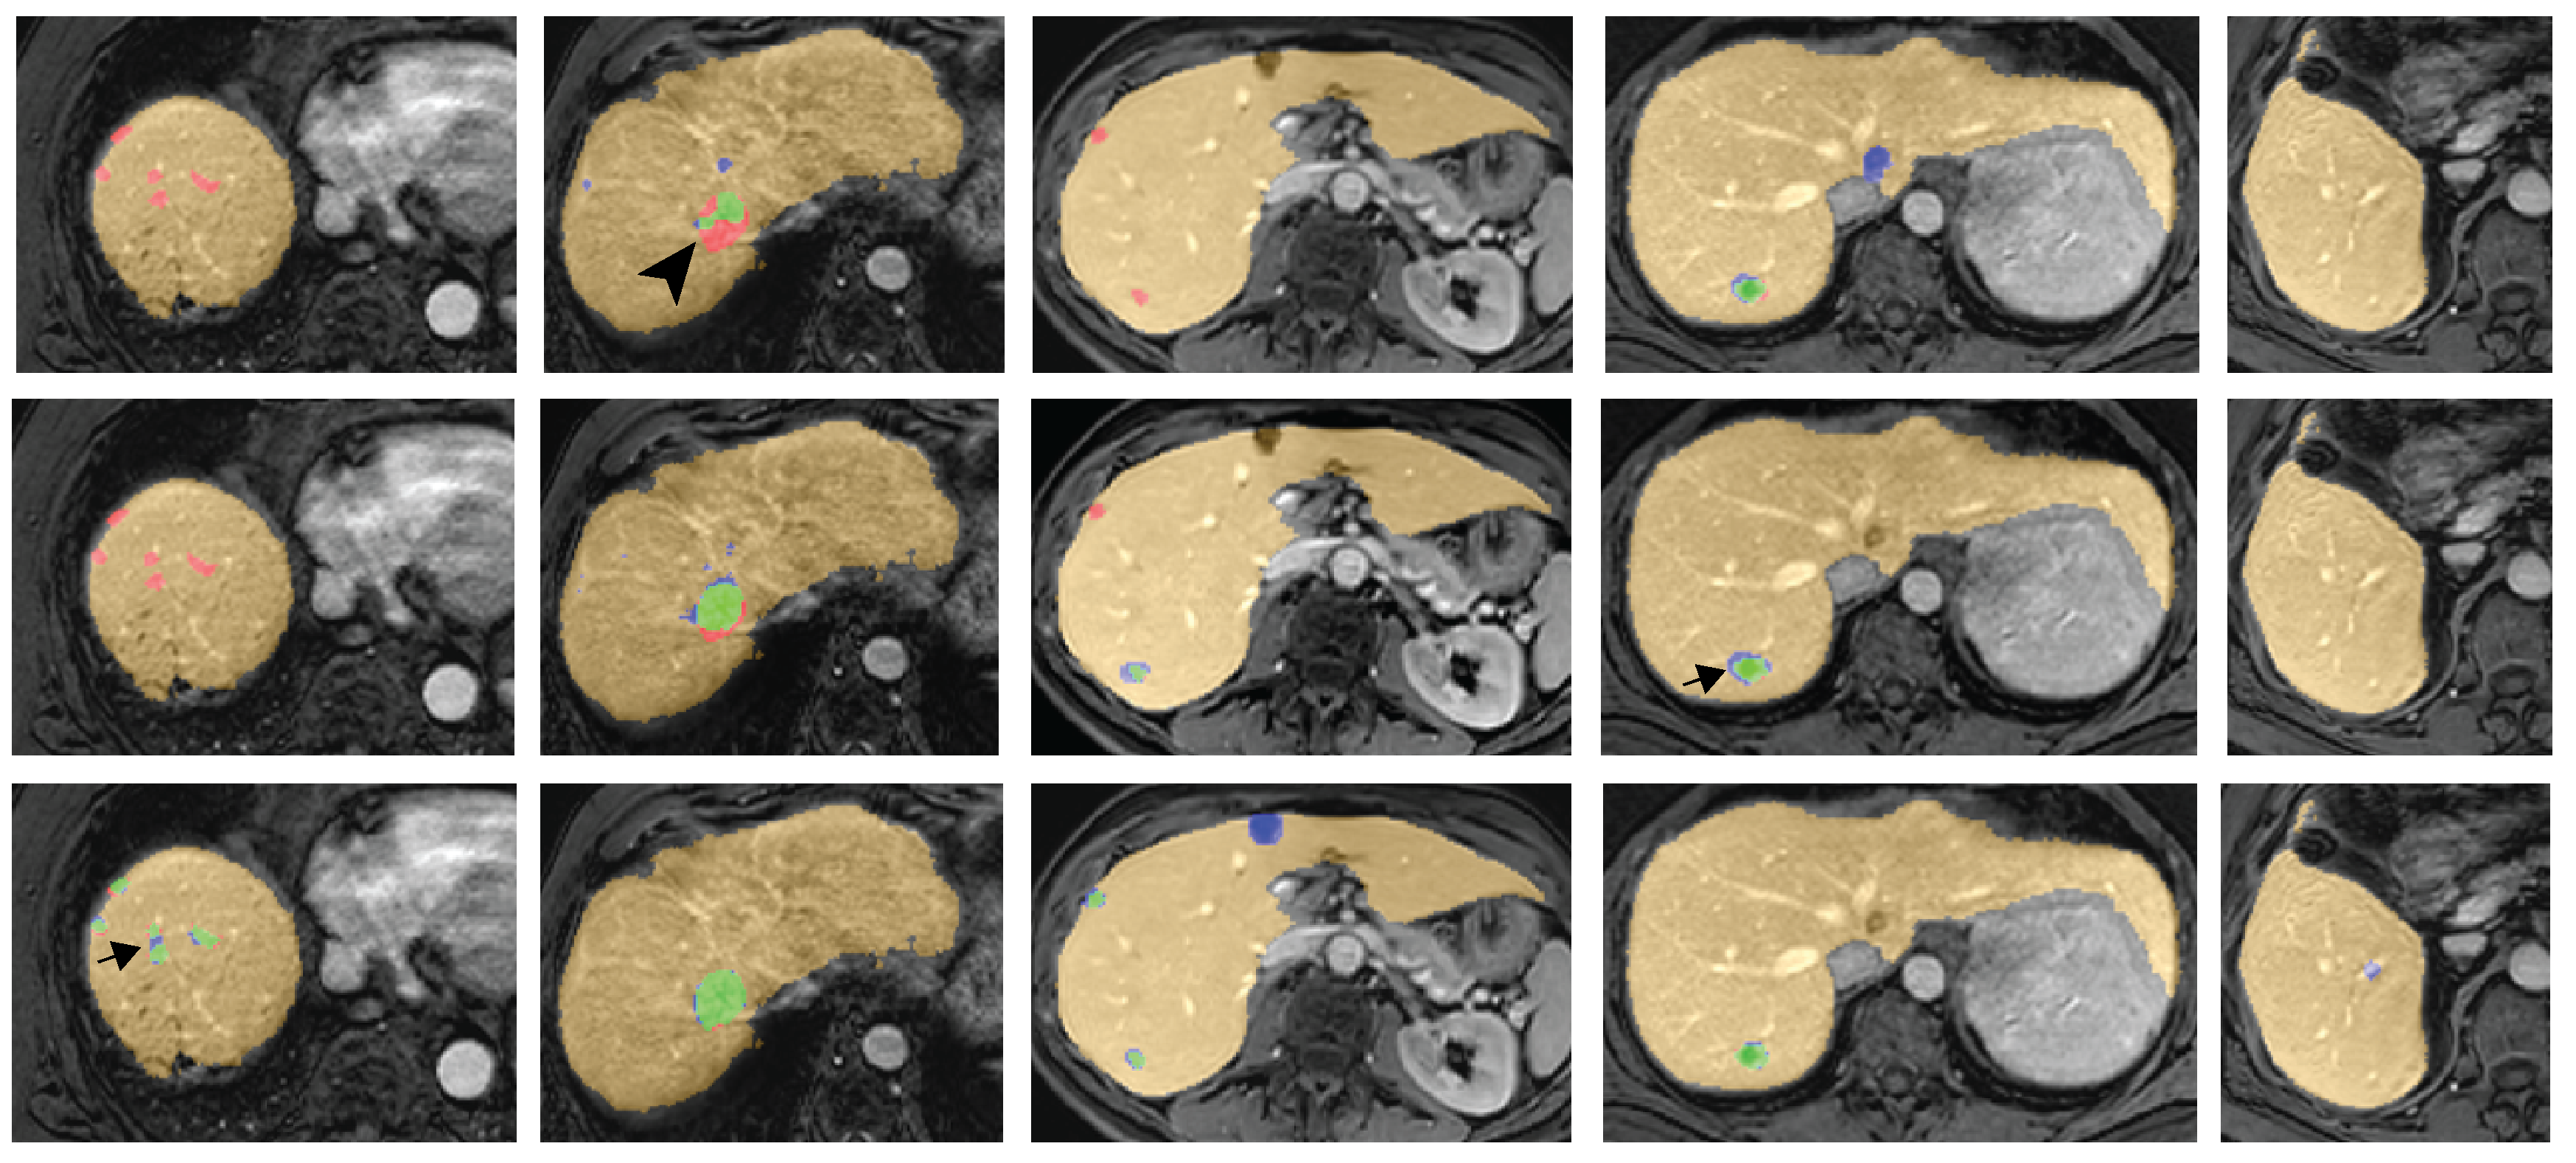

Fig. 3 shows some examples of the late arterial phase of the DCE-MRI, the DW-MRI with b-value 150 s/mm2, the manually annotated liver and metastases, and the automatic segmentation of the liver with the detection of the liver metastases involving both DCE-MR and DW-MR images in the dual pathway FCN. It shows good liver and lesion segmentations, with a false positive object in the last row, which is verified to be a cyst.

Fig. 8 shows five examples of the lesion detection results including the liver segmentation result. The green pixels are true positive, blue pixels are false positive, and red pixels are false negative. Note that true positive objects are connected components that overlap with a manually annotated metastasis. A true positive object can nonetheless have some undersegmentation (red pixels, example indicated with arrow head) or oversegmentation (blue pixels, example indicated with arrow).

The missed metastases by the single pathway networks are mostly smaller than 2 cm³, as can be seen in Fig. 6. These smaller metastases may differ in appearance from larger ones, because certain features, such as rim enhancement, cannot be expressed in only a few voxels of the DCE-MR images. The network with only DCE-MR input images is uncertain about these metastases, which leads to low outcome probabilities. However, the single pathway with both DCE-MR and DWI-MR is also less able to detect these smaller metastases. The network seems to fail to create adequate feature maps to detect small metastases, when it combines the two MR sequences in the first convolutional layer. The dual pathway network is allowed to create feature maps for the two MR sequences separately. The phases of the DCE-MR images are correlated over time, as are the three b-value images of the DW-MR. Both MR sequences contain useful characteristics. In the dual pathway network, the feature maps are solely composed of the MR sequence presented to that pathway, representing those characteristics. And the feature maps are combined at the end. This might explain the difference the detection of the small metastases of the two networks. In addition, the dual pathway has two times more parameters as the single pathway. Fig. 8, first column, shows some examples of sub-centimeter sized metastases.

The dual pathway network detects almost all metastases, but also incorrectly marks other objects as metastases. Most of these false positives are caused by objects which are not or scarcely represented in the training set and have thus an appearance unknown to the network. These unknown appearances could be other lesions and liver conditions, such as cirrhosis or an inhomogeneous fat distribution in the liver. The network has mostly seen healthy liver parenchyma with metastases during training and has learned to distinguish these, but is uncertain about conditions and lesions not seen during training. Fig. 3 (last row) and Fig. 8 (third column) show examples of cysts marked as a metastasis by the detection method.

Inspection of the 19 false positive objects for a threshold level of 0.90 in the post-processing step reveals that 10 of the false positives are lesions: 9 cysts and 1 hemangioma. Three of the false positives are blood vessels and one false positive is because of an inhomogeneous fat distribution in the liver. Fig. 8 (last column) shows an example of a blood vessel marked as a metastasis. Three other false positives are located on the edge of the liver, which sometimes has a higher intensity than the rest of the liver (e.g. Fig. 3 second column). Furthermore, motion artifacts can be the cause of a false positive object, which is the case for two false positives.